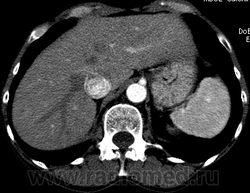

Пациентка Г. 1959 г/р, обратилась амбулаторно в Гатчинскую ЦРКБ на МСКТ брюшной полости, по направлению поликлиники, диагноз: "Образование правой доли печени". По данным УЗИ: гипоэхогенное образование в правой доле печени (сегмент не указывают) 1,1 * 1,1 см; диффузные изменения ПЖЖ, двусторонний нефроптоз. КТ рекомендовано специалистом УЗД.

Сегодня, 3.07.13., выполнена МСКТ органов брюшной полости с болюсным контрастированием (омнипак-300 - 100 мл) на программе "3 фазы печени"

На преконтрастной серии - впечатление о расширении нижней полой вены.

В артериальную фазу - интенсивное накопление контраста, как раз в области этого расширения, в 4-5 сегментах печени.Выше и ниже - идет неизмененная НПВ, без контраста (фаза артериальная!) В венозную фазу - небольшая гиперденсная зона перикавально в печени - и все.

Этот участок патологического накопления контраста имеет размер 2,5 * 2,5 см, никак не 1,1 * 1,1(как дают УЗИ-сты)

На 3d-реконструкциях выглядит как кавернозная гемангиома, по форме напоминающая желчный пузырь (который я, кстати, не вижу, а УЗИсты описывают) Если это - ж.п., почему так интенсивно копит контраст, и вообще, расположение такое нетипичное?

Образование печени ли это вообще? Не перикавальное внепеченочное нечто? (и что?)